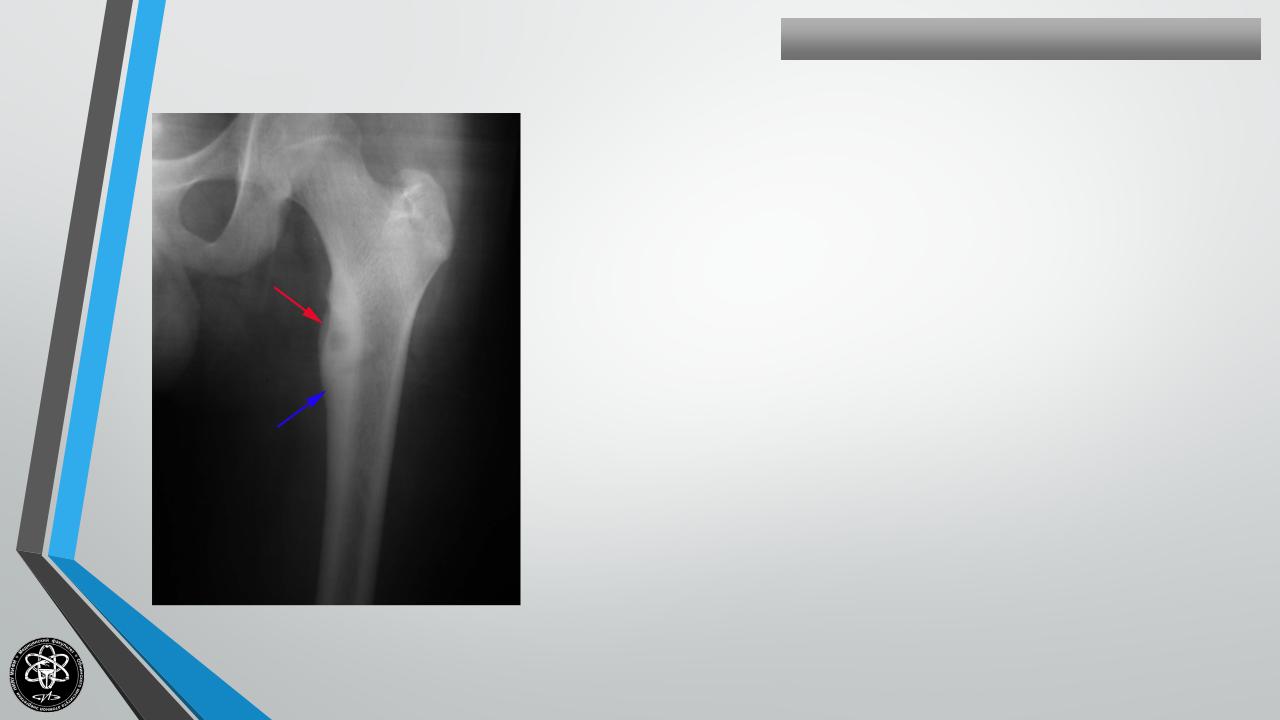

ОСТЕОИД-ОСТЕОМА

Частота — 4 % всех опухолей скелета.

Поражаемый возраст — 20-30 лет.

Излюбленная локализация — большеберцовая и малоберцовая кости, но может локализоваться в локтевом отростке и др. костях.

Клиника — выраженный болевой компонент. Иногда боли носят мучительный характер. Выраженное нарушение функции.

Рентгенологическая картина — зона просветления, окруженная ободком склероза, в центре часто секвестр.

Гистологически — полость, выстланная грануляционной тканью, в центре — секвестр, достигающий величины горошины.

Лечение хирургическое — краевая резекция кости в пределах здоровой ткани.

Исход — выздоровление. Рецидивы редки. Озлокачествления не наблюдается.